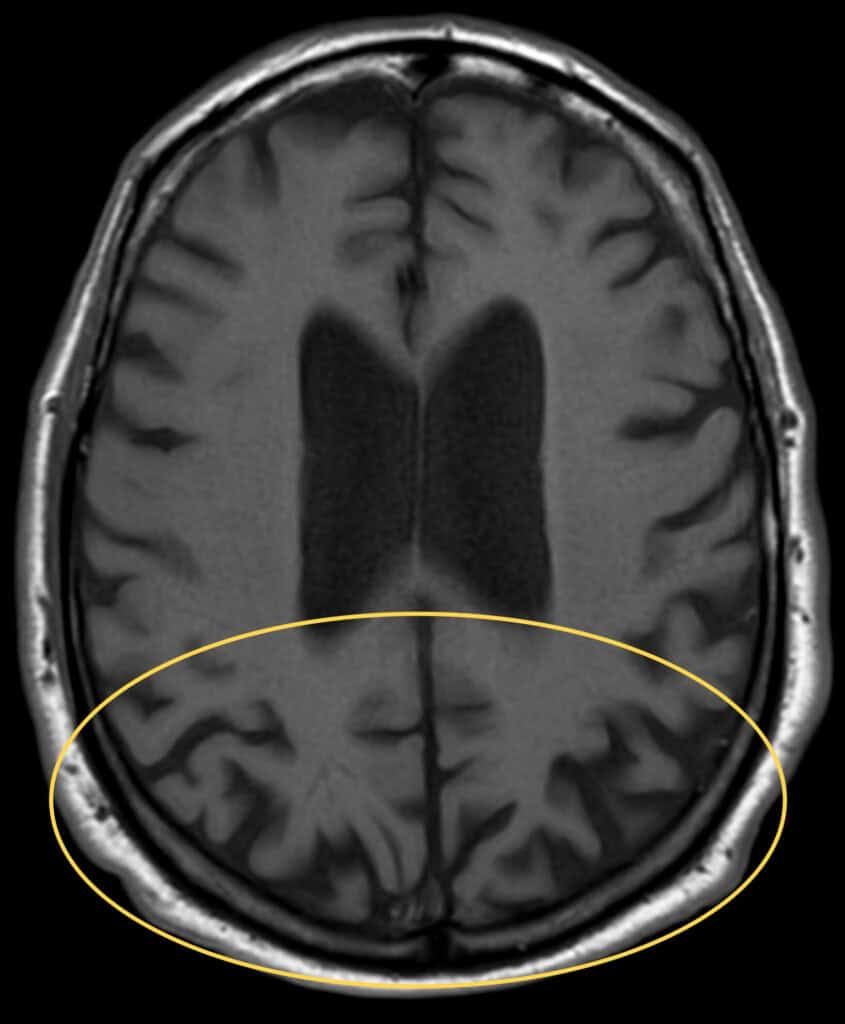

A neuropsychology evaluation was performed ten days after the initial encounter. The report stated the patient had stopped driving over two years prior due to “vision issues.” Given the age of onset and timeline of visual symptoms starting prior to memory loss, this evaluation suggested a diagnosis of PCA. The PCP later diagnosed Alzheimer’s disease, dementia, and prescribed memantine. It is speculated that the diagnosis of AD was made to address the memory loss for which the PCP was following the patient prior to available MRI findings. An MRI performed one month later showed central cortical atrophy, more prominently in the parietal and occipital lobes (Figure 2) and was otherwise unremarkable.

Figure 2. Transverse T1-weighted brain MRI image shows bilateral cortical thinning and sulcal widening in the bilateral occipital and posterior parietal regions (yellow oval).

There is no consensus on how to diagnose PCA, however, physicians rely on advanced neuroimaging to rule out other etiologies (e.g. stroke or tumor), along with the commonly found characteristics of PCA. Brain MRI can detect atrophy which predominantly affects the occipital, parietal, and posterior temporal lobes in PCA compared to the more diffuse cortical atrophy as observed in typical AD.2,3,18 Functional neuroimaging, such as single photon emission computed tomography (SPECT) and fluorodeoxyglucose positron fludeoxyglucose positron emission tomography (FDG-PET), may depict hypoperfusion and hypometabolism, respectively, of the occipito-parietal cortices.18,21